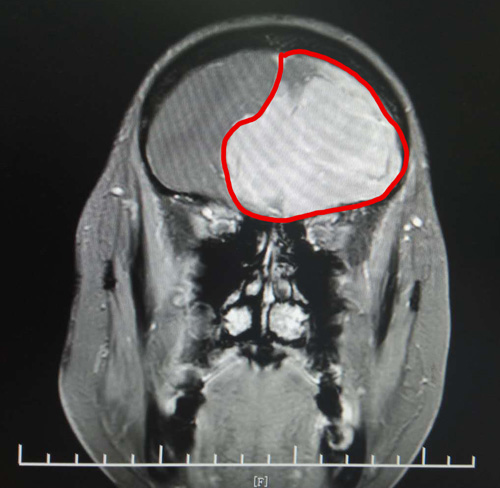

頭顱MRI增強(qiáng)顯示,丁阿姨的前顱窩有巨大的團(tuán)塊狀異常信號(hào)。腫瘤大小約為6.9×5.6×5.4厘米,其大小與鴨蛋接近。

頭顱MRI影像清晰顯示了巨大的腦膜瘤

由于巨大腫瘤壓迫患者不少重要的神經(jīng),腫瘤已將周?chē)DX組織結(jié)構(gòu)和主要腦供血?jiǎng)用}擠壓得嚴(yán)重變形,手術(shù)難度很大。